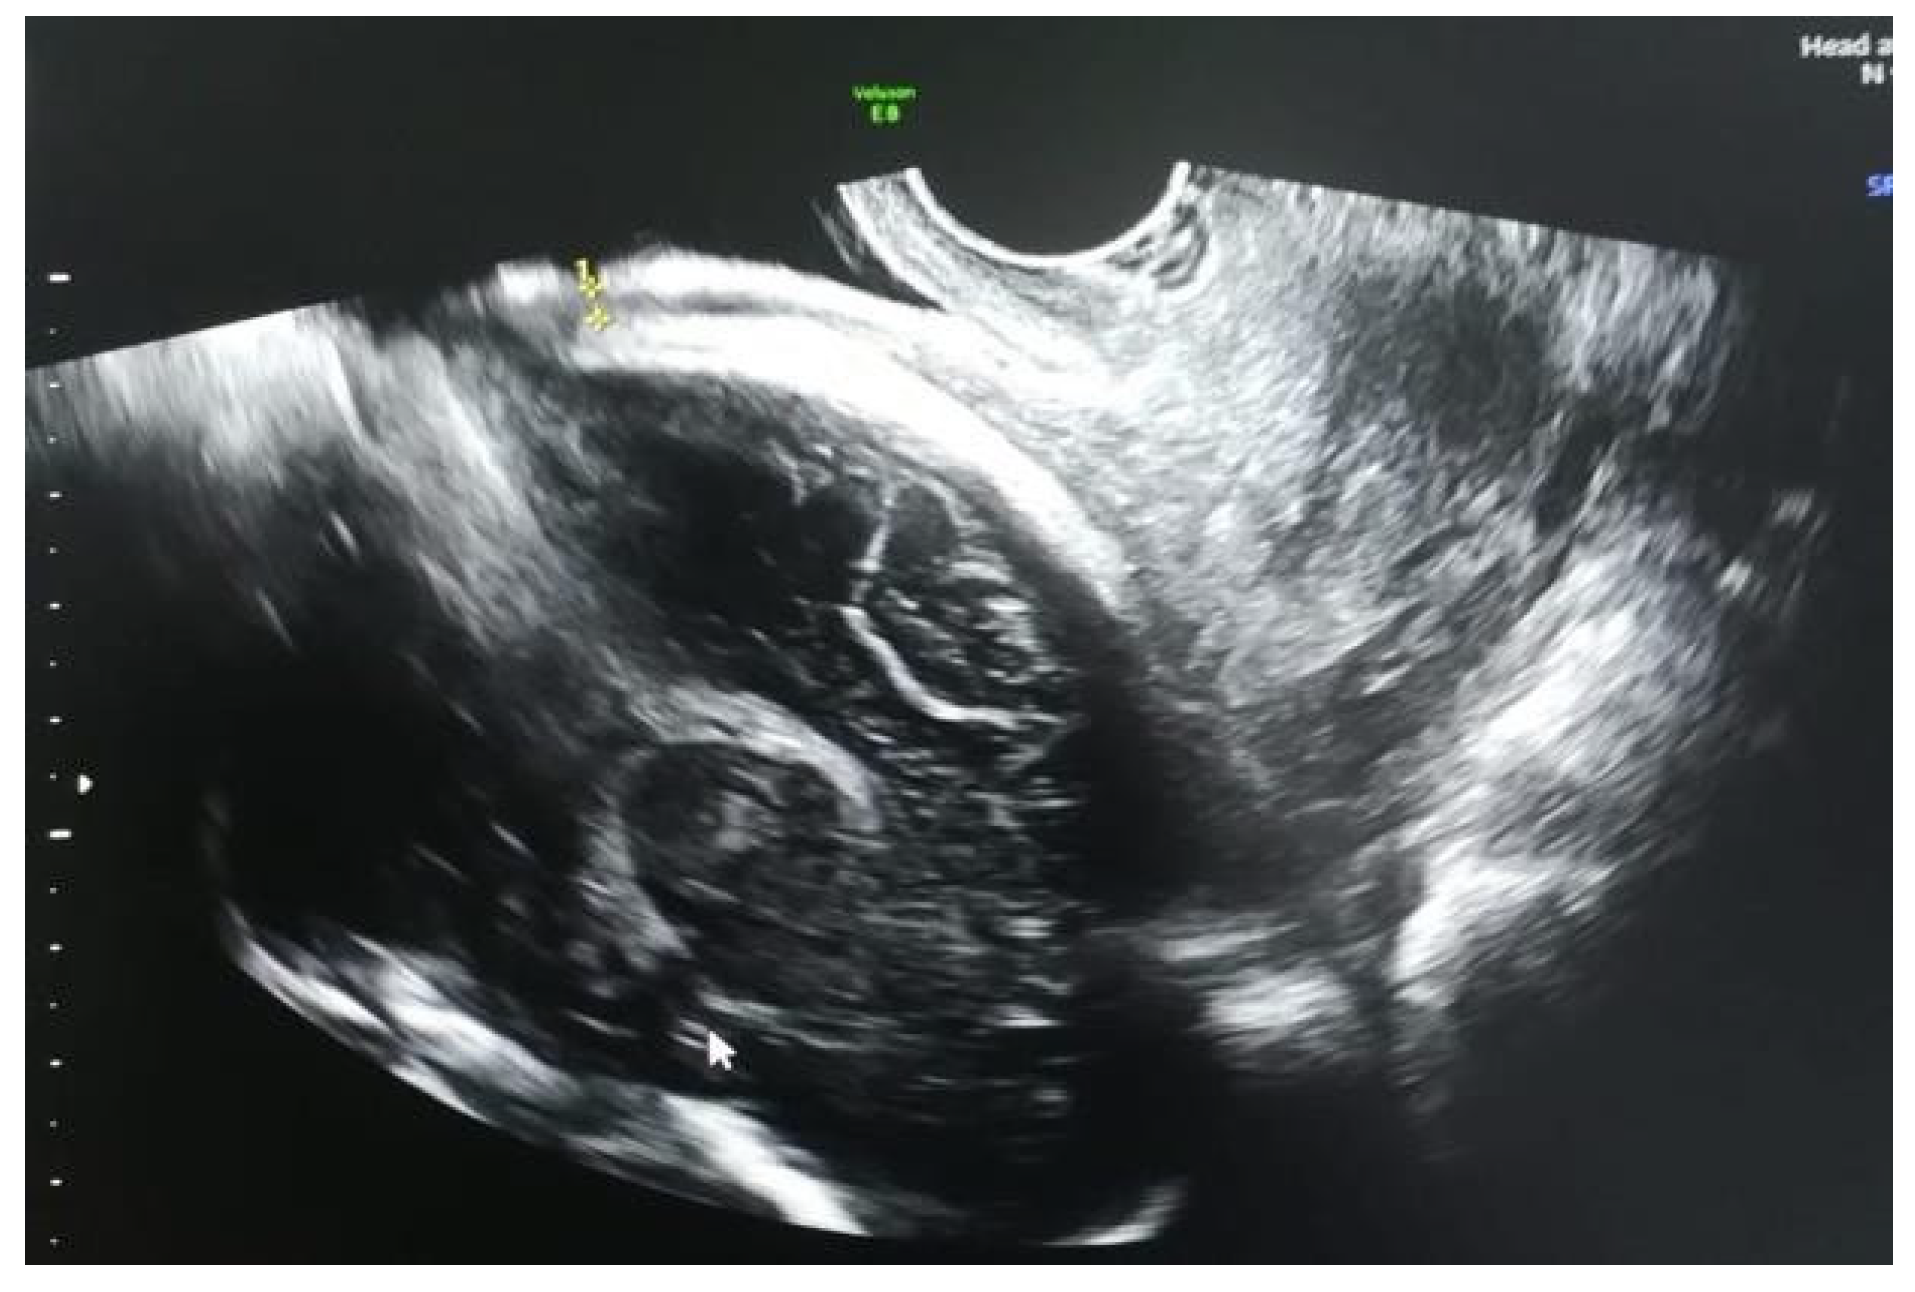

- The predictive ultrasound parameters for the risk of rupture/dehiscence of the uterine scar showed varying cut-off values, ranging between 2.0 and 3.5 mm for the lower segment and up to 0.97 mm for the myometrium.

- This observation of inverse proportionality between the uterine thickness and the risk of rupture/dehiscence of the scar seems to be correlated with the histopathological features of the cesarean section scar.